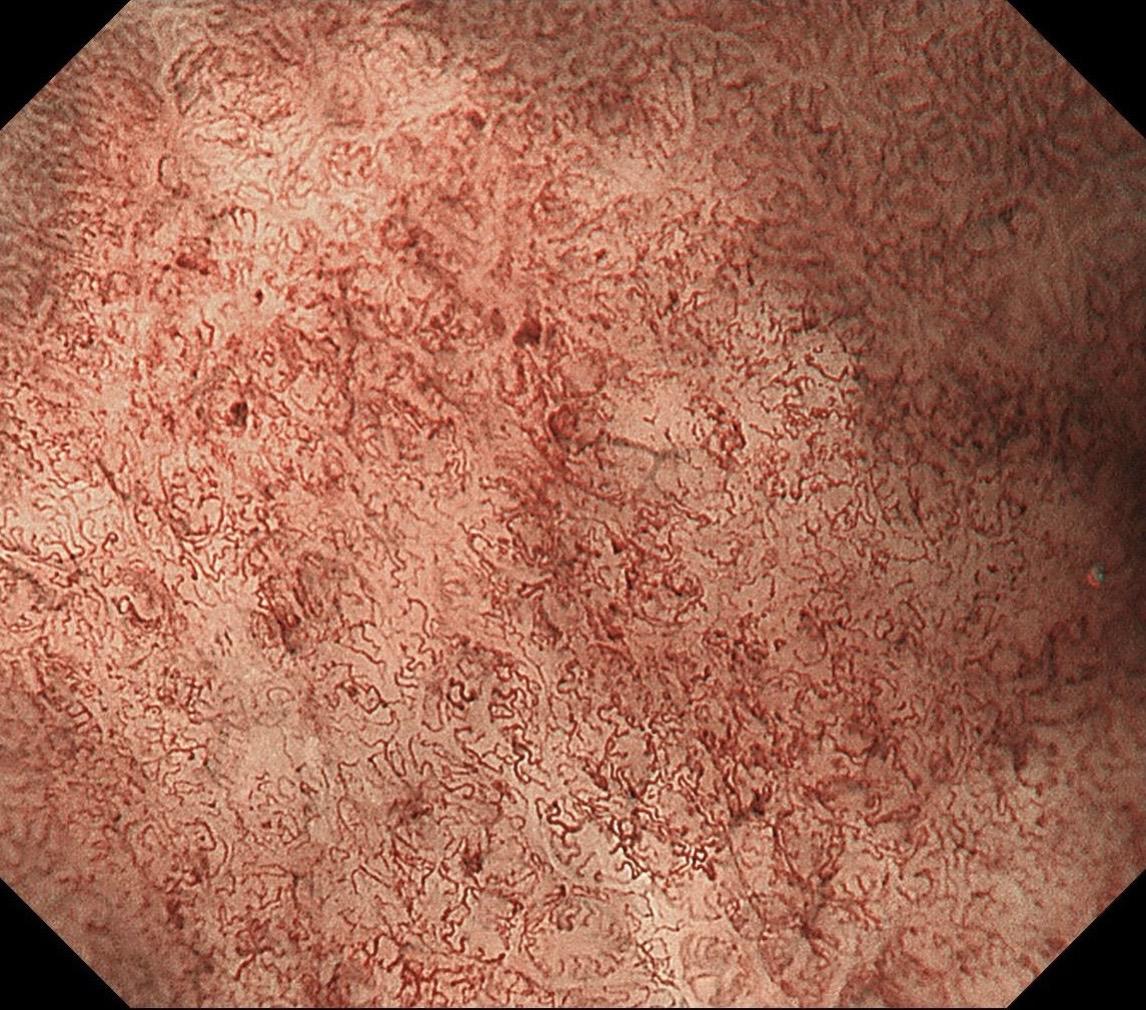

男,40岁,胃双发褪色调病变。慢性胃炎复查,3年前胃镜未见异常,Hp阳性背景,萎缩不明显,胃体下部大弯见一褪色调病变,浅凹陷,5mm左右,换用放大内镜观察,表面结构缺失,血管异型明显,未分化可能性大……胃窦后壁见一白斑,无高度差,NBI浅茶色,放大草草看了下,似有边界,IP增宽,活检待病理……小哥哥胖得几乎没脖子,腹式呼吸太明显~😖